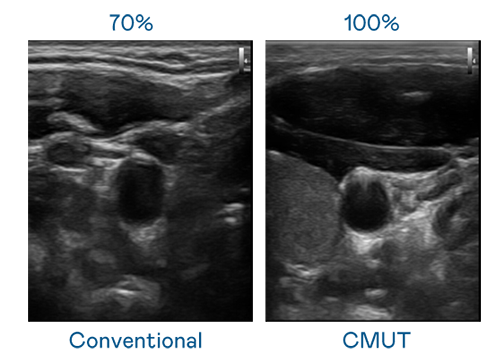

CMUT 技術是一種用電容式微機電元件來產生超音波訊號的技術。與傳統 PZT 壓電式技術相比,CMUT 頻寬增加 30%,更寬頻的超音波訊號讓影像解析度大幅提升,是實現高影像品質醫療超音波掃描、促進精準醫療發展的關鍵技術。

大頻寬帶來超清晰影像

超音波影像的解析度高低,首先取決於探頭能發出的訊號頻寬。JJB电竞 CMUT 可提供高清晰的超音波訊號,提供高頻寬、高靈敏度、影像紋理細節更高的超音波影像,協助醫護人員縮短影像判讀時間及利用精準的醫療影像進行診斷。